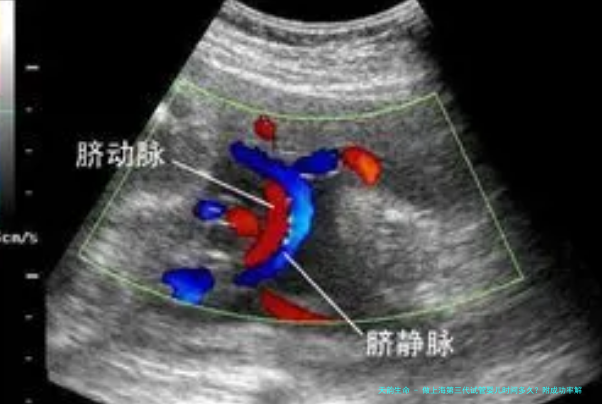

进入试管婴儿周期来临前,夫妻两方需要好行全方位的身体检查。检查女性的子宫和卵巢的情况是否适合怀孕,是不是吻合第三代试管婴儿的适应症,查验时间是1个月左右。如果女性年龄较小,两边身体情况也比较好,医生会建议自然受孕或是人工授精。